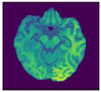

A brain tumor can be defined as a cancerous or noncancerous mass or development of abnormal cells in the brain. Gliomas can be categorized into High-Grade Glioma (HGG) and Low-Grade Glioma (LGG), based on the pathological assessment of the tumor. Brain tumor segmentation seeks to separate healthy tissue from tumorous regions. This is a crucial step in analysis and treatment planning to improve the possibility of effective treatment. Nowadays, biological science has emerged with several extended research problems under the category of Digital Image Processing (DIP). The detection of the tumor and its classification, detection of the cancerous region and its classification, testing, and inspecting crucial parts of the human body are some applications that fall under this category. Out of various medical science problems, automatic brain tumor segmentation and detection is of utmost importance, and efforts are being made in order to effectively handle this problem. A January 2020 Cancer.net editorial approved a report that estimated that this year, 23,890 adults, i.e., 13,590 males and 10,300 females, will be identified with cancerous tumors of the brain and spinal cord in the USA. In general, brain tumor diagnosis usually starts with Magnetic Resonance Imaging (MRI). The suspicious regions are separated using magnetic resonance segmentation using a complicated clinical imaging process. MRI is the most commonly used process that highlights the tumorous region in the brain, although brain tumor detection is still a manual process, examined and validated by experts. Thus, we require a compelling process to identify brain tumors in the early stage to save patients with high accuracy. There are some issues in the manual process, due to which the automatic detection of brain tumors becomes pivotal. Computer-aided detection of abnormal growth of tissue is primarily motivated by the necessity of reducing human error and thus achieving maximum possible accuracy. Using automated algorithms for the accurate and robust predictions of overall survival for patients diagnosed with gliomas can provide valuable guidance for diagnosis and necessary treatment. Furthermore, there is a lack of skilled Oncologists and Neurologists, especially in developing countries. According to a report in 2018, the country is facing a severe shortage of caregivers, with merely 2000 oncologists looking after around 10 million patients (https://timesofindia.indiatimes.com/india/India-has-just-2000-oncologists-for-10-million-patients/articleshow/50842842.cms). Owing to the presence of abnormalities, no conventional technique can be developed for the segmentation of brain tumors in the medical field. Generally, magnetic resonance image (MRI) scans are utilized for the proper examination and diagnosis of brain tumors. This study systematically works on the detection of brain tumors using MRI images []. Owing to the profound significance of machine learning and deep learning, a vast number of methods have been developed, mostly using a specific technique, i.e., machine learning or deep learning []. Despite initiating a breakthrough in handling tumor detection tasks, existing applied deep learning models have some drawbacks. CNN-based deep learning techniques require high volume data, which makes it a complex and expensive task. Massive features are necessary to train tumor detection and segmentation accurately. However, the U-net model of CNN has shown great help in prognosticating in medical image segmentation. In recent literature, numerous works are done either using variation in U-Net architecture or with some pre/post-filtering for outcome improvisation. A Multi-Inception-UNet architecture is proposed to improve scalability and is applied to BraTs 2015, 2017, and 2019 datasets []. This is considered the latest work done in this same direction with the help of this same U-Net Model. MRI Brain Tumor segmentation is validated using 3D-UNet on the BraTs’20 dataset, where the author achieved an accuracy of 0.83 on the training set and 0.82 on the validation set []. The proposed work is somewhat motivated by the work done by Jurdi et al. in June 2020; in their work, U-Net with Bounding Box Prior is applied to two public datasets—SegTHOR is Computed Tomography (CT) images and another Cardiac dataset is a mono-modal MRI dataset. A bounding box (BB) filter is inserted at the BBConV Layer, by which researchers can achieve approximately 98.32% average dice coefficient []. Henceforth, in this study, a systematic process is performed for the detection of brain tumors using MRI images. The experimentation uses U-Net to exhibit the knowledge of deep learning models for tumor image segmentation. The deep learning model is applied for MRI segmentation on the BraTS 2018 dataset (https://www.med.upenn.edu/sbia/brats2018/data.html), which contains four different MRI modalities—T1, T2, T1Gd, and FLAIR of each patient (see Figure 1).

Figure 1.

A sample set of T1, T1-GD, T2, and T2 Flair images (Source: BraTS 2018 Dataset).

Corresponding to each patient, the segmented tumor region and OT (ground truth of tumor segmentation) are stated. Although experiments are primarily carried out on the BraTS dataset, a list of datasets used to perform brain tumor detection tasks is also tabulated in Table 1 for the readers’ point of view.